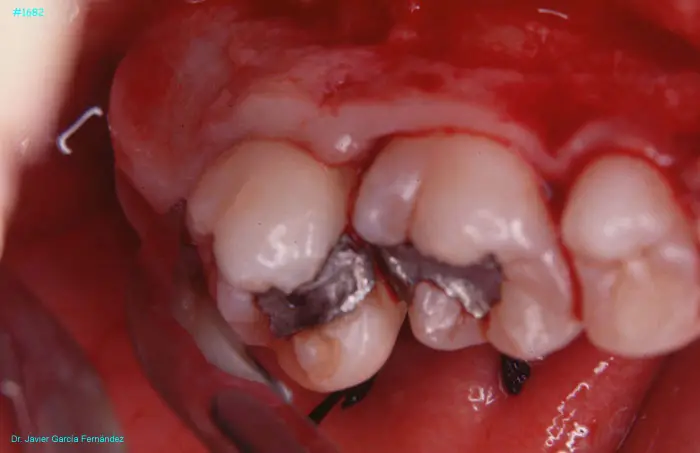

Atlas of Surgical Techniques in Periodontics. Chapter IV. Atlas de Técnicas Quirúrgica en Periodoncia

image 194